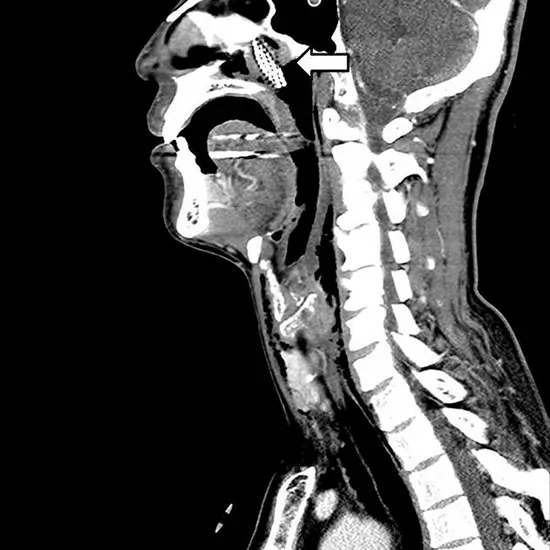

An MRI of the neck and PNS shows the cervical spine, which comprises seven cervical vertebrae and the soft tissues around them (blood vessels, lymph vessels, and nerves). The scan is used to look for tumors, slipped discs, and aneurysms.